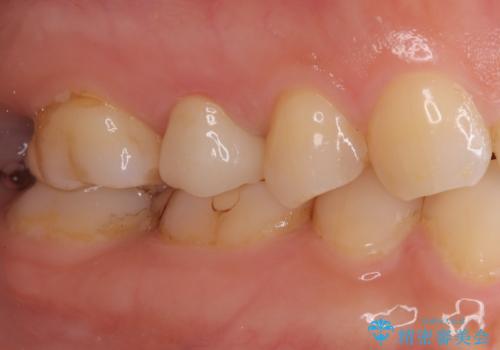

【オールセラミッククラウン】根管治療も行いたい。

- 右上の歯が、噛むと痛いことを主訴に来院されました。

ラバーダムと顕微鏡を用いた根管治療を希望され、治療後は痛みも改善することができました。

その後、オールセラミッククラウンにて修復を行っています。

顕微鏡を用いて根管治療を行うことで、破折の有無などを判断しやすくなります。